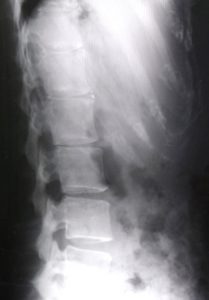

整形外科ではほとんどの場合,腰のレントゲンを撮影し,

診断の判断材料の一つとされています。

レントゲンを診て,

『骨と骨との間が狭いから,腰の椎間板ヘルニアだね』

と言われることが多いようです。